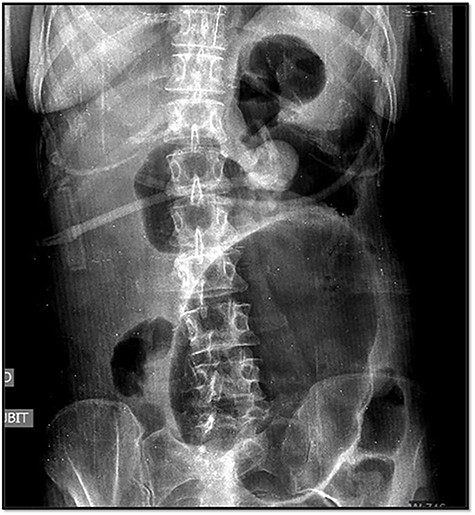

The emergency blood test showed a normochromic and normocytic anemia with an hemoglobin of 10.1 mg/dl and a leukocytosis of 11.150/ul with 70% neutrophils. The abdominal radiography showed a prominent dilation of a small bowel loop. The CT scan reported an 18-cm dilated loop. The main diagnostic suspicion was a small bowel volvulus without signs of ischemia or perforation (Figs 1–3).

In the abdominal X-ray, one of the three typical signs can be observed: dilation of the cecum, a single air-fluid level in the upper left quadrant of the abdomen or the absence of gas in the colon.